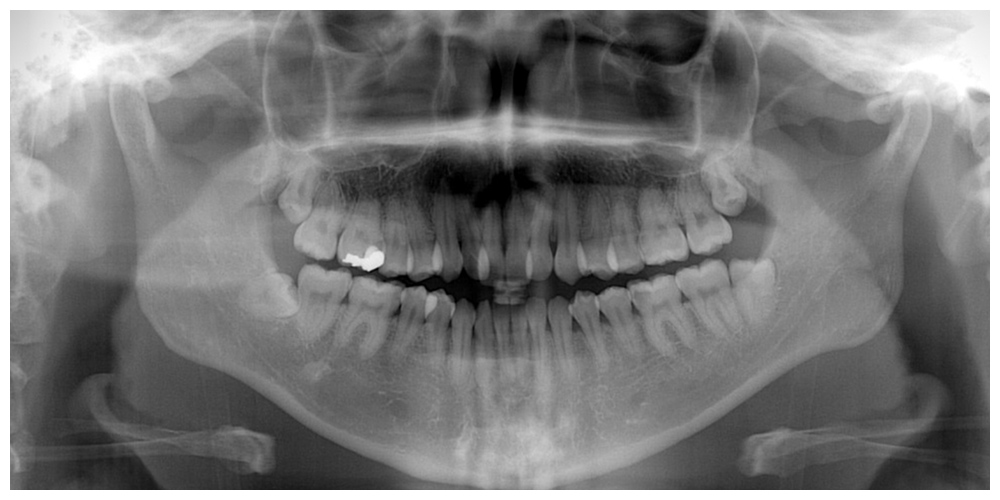

マウスピース矯正(インビザライン)で理想的な歯並びを実現するためには、正確な歯型の採取が非常に重要です。当院では、口腔内の3次元データを詳細にスキャンしてデータ化できる「iTero element 5D」を導入しています。この技術により、従来のシリコンを使った歯型採取と比較して、より精密で正確な歯型を取得でき、理想的な歯列を作り上げるための高精度な治療を提供しています。

レントゲン写真を元に、

歯並びと顎骨の分析をします

矯正カウンセリングにお越しいただいた方を対象に、WEBCEF(ウェブセフ)よる歯列矯正の解析レポートを作成し、詳しいご説明の上でご提供します。